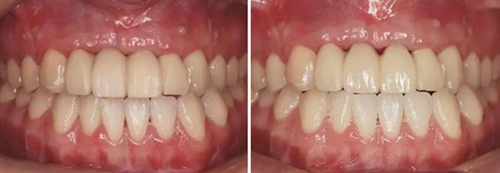

③患者試戴個(gè)性化氧化鋯基臺(tái),檢查基臺(tái)就位情況,咬合狀況,基臺(tái)邊緣位于齦緣下<1mm,試戴氧化鋯基底,確認(rèn)基底就位良好,邊緣密合,完成永久修復(fù)體的制作。口內(nèi)戴入氧化鋯基臺(tái)后,扭矩扳手加力至30N后,聚四氟乙烯封閉螺絲通道,樹脂封孔。試戴全瓷修復(fù)橋體,檢查冠邊緣與基臺(tái)邊緣緊密接觸,與周圍軟硬組織相協(xié)調(diào),確認(rèn)鄰接以及修復(fù)體顏色良好。調(diào)整咬合,靜態(tài)咬合:正中咬合時(shí)后牙區(qū)均勻接觸,輕咬合時(shí)前牙區(qū)無接觸,重咬合時(shí)輕接觸,無牙合干擾或早接觸;動(dòng)態(tài)咬合:側(cè)方運(yùn)動(dòng)時(shí)尖牙引導(dǎo)或前牙組牙功能的交錯(cuò)保護(hù)牙合,前伸運(yùn)動(dòng)是切牙引導(dǎo)牙合,工作側(cè)和非工作側(cè)無牙合干擾。咬合調(diào)整完畢后高度拋光,口外用硅橡膠制備預(yù)粘接代型,超聲振蕩修復(fù)體,消毒后使用自粘接樹脂水門汀于口外預(yù)粘接并戴入口內(nèi),使用牙線去除多余粘接劑。拍攝X線片,確認(rèn)基臺(tái)和牙冠完全就位。

圖37 戴入全瓷修復(fù)體局部舌側(cè)觀 圖38 永久修復(fù)后微笑

圖39 永久修復(fù)后大笑

3、通過制作個(gè)性化轉(zhuǎn)移桿,將種植體周圍軟組織的形態(tài)輪廓精確地復(fù)制并轉(zhuǎn)移到模型上,個(gè)性化制作的氧化鋯基臺(tái)及全瓷修復(fù)體,生物相容性及美學(xué)效果良好,患者對(duì)最終修復(fù)效果滿意。